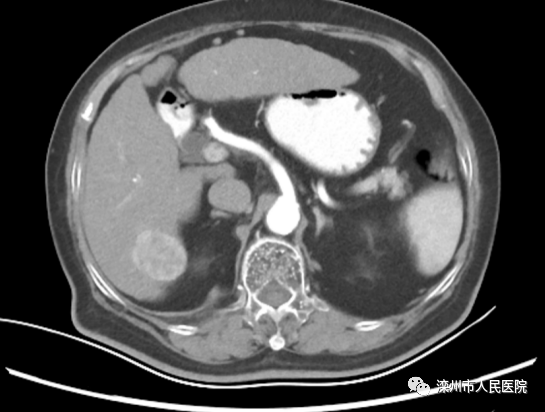

術(shù)前影像